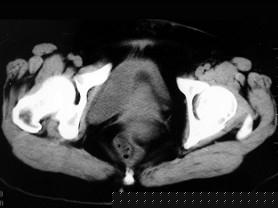

问题 女 ,32岁 ,因停经46天 ,少许不规则阴道流血15天 ,下腹胀痛 3 天入院,后穹窿穿剌抽出不凝血,CT检查如图所示,下列说法错误的是 ( )

选项 A、此为宫外孕 B、此为卵巢巧克力囊肿 C、病灶外缘较光整 D、盆腔内较高密度积液 E、在左附件区可见一椭圆形略高密度病灶

答案 B